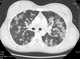

Varicella pneumonia

Chickenpox, also known as varicella, is a highly contagious disease caused by the initial infection with varicella zoster virus (VZV). The disease results in a characteristic skin rash that forms small, itchy blisters, which eventually scab over. [Source: Wikipedia ]